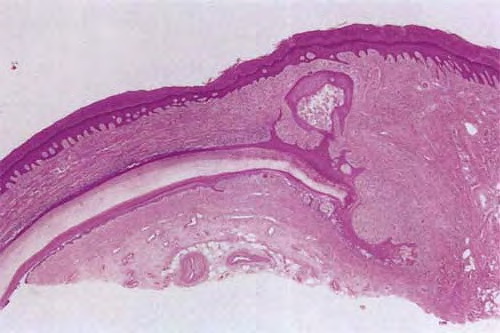

Histopathology

The lesions are termed lentiginous because the majority of the lesional cells are single and located near the dermal-epidermal junction, especially at the periphery of the lesion . However, usually some tumor cells can be found in the upper layers of the epidermis, especially near areas of invasion in the center of the lesions. The histologic picture differs from that of lentigo maligna because of irregular acanthosis, the lack of elastosis in the dermis, and the frequently dendritic character of the lesional cells . Early in situ or microinvasive lesions may show, especially at the periphery, a deceptively subtle histologic picture consisting of an increase in basal melanocytes and hyperpigmentation with only focal atypia of the melanocytes. However, in the center of the lesions, there is usually readily evident uniform, severe cytologic atypia. There may be a lichenoid lymphocytic infiltrate that may largely obscure the dermal-epidermal junction, and in some cases this may be so dense as to simulate an inflammatory process. In most of the lesions, both spindle shaped and rounded, pagetoid tumor cells are seen, and, in many cases, pigmented dendritic cells are prominent. Pigmentation is often pronounced, resulting in the presence of melanophages in the upper dermis and of large aggregates of melanin in the broad stratum comeum. As in lentigo maligna, when tumorigenic vertical growth phase is present, it is often of the spindle cell type and not uncommonly desmoplastic and/or neurotropic. In other instances, the invasive and tumorigenic cells in the dermis may be deceptively differentiated along nevoid lines.